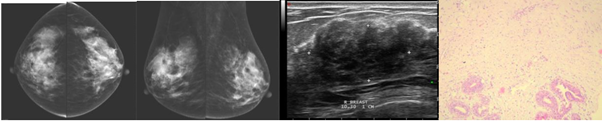

A 65-year-old female presented with painless left breast lump since 1 week before. There was history of DM for 20 years. Physical examination revealed 2cm, indistinct border, and low movable mass suggesting malignancy.

Mammography showed asymmetric density in left breast. US showed irregular hypoechoic mass, taller than wider, which on doppler showed no intravascularization, BI-RADS: C5.

Excisional biopsy with frozen section was carried out revealed extended solid fibrous tissue, hard consistency and irregular margin without any nodule. Microscopic examination revealed fibrocollagen stromal proliferation and mature fat tissue, consisted of lobules with ductal dilatation and compression, surrounded with lymphocyte infiltration. There were no signs of malignancy (Figure 2).

Figure 2 Mammography, USG, and histopathologic findings of a 65-year-old female presented with left breast lump turned out to be DMP.